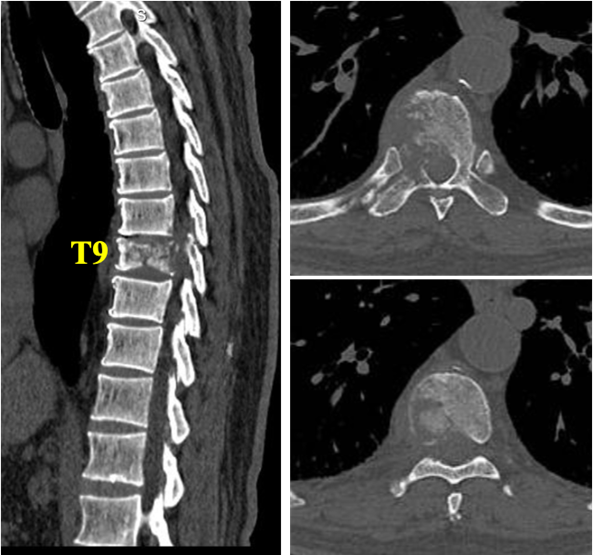

2025-6-12 胸椎三维CT(图1):T9椎体及右侧椎弓见骨质破坏,病理性骨折。

图1:胸椎三维CT